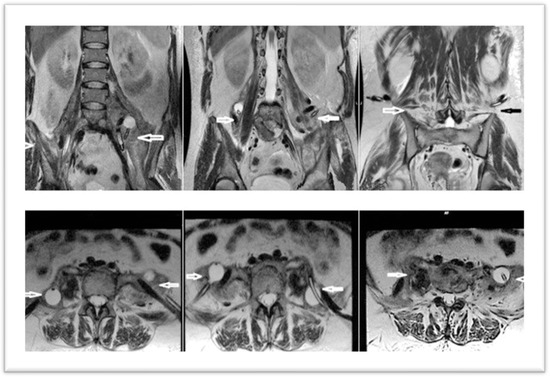

In February 2023, the patient was admitted to the clinic. An MRI of the lumbar spine was performed upon admission. It revealed multiple injuries, but with the preservation of certain structures intact: erosive changes, with association of fluid densities, located at the level of the intervertebral disks (diskitis L4–L5 and L5–S1); multiloculated collections in the psoas muscles bilaterally, 230/79 mm (cc/ll) left and 200/82 mm (cc/ll) right, without clear signs of extension at the epidural space; vertebral bodies, aligned at the anterior and posterior wall; overlying intervertebral disks with preserved height and not exceeding the vertebral contour (Figure 1).

Figure 1. MRI images at admission—sagittal and transverse sections—arrows indicate the two collections, left and right.